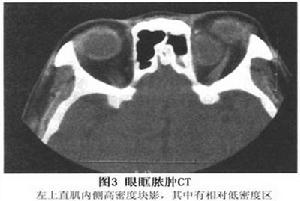

2.CT掃描 眶內見類圓形或不規則形高密度環影,邊界清可伴周圍脂肪密度增高眼球壁增厚,眼外肌被遮蔽或視神經增粗。鼻竇密度增高,黏膜增厚,有時可見液平面,說明膿腫繼發於鼻竇炎。CT還可發現異物存留的位置,尤其是金屬異物,植物性異物經常顯示為低密度。